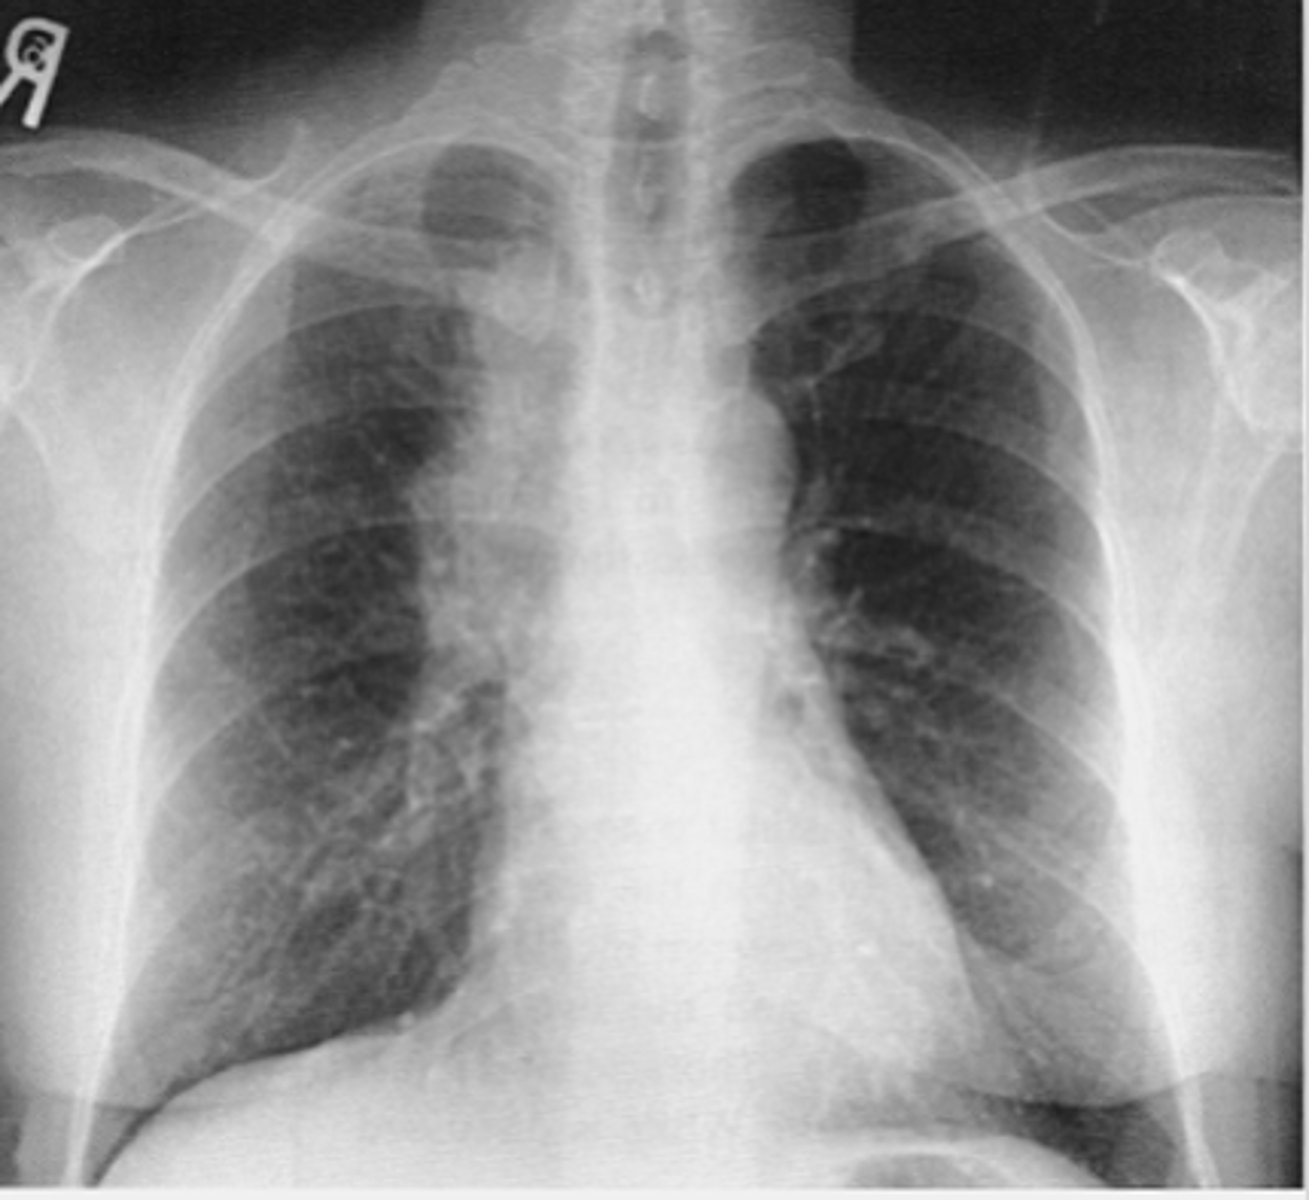

Moderate CHF with:

-redistribution of pulmonary vasculature (pulm vasculature should not be visible at all, esp in apices, but they are visible here)

-cardiomegaly and L sided pleural effusion

Dx - what kind of CHF is this?

<p>Dx - what kind of CHF is this?</p>